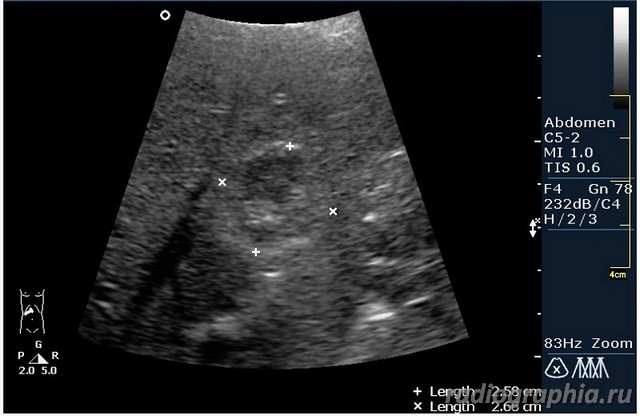

УЗИ печени. Женщина 37 лет. Жалобы на боли в эпигастрии; в печени обнаружено такое образование...

Считаю,что это опухоль,имеет неоднородную структуру,четкий контур,прорастает в сосуд(есть один такой скан) И,вообще,вся поверхность печени НЕСПОКОЙНАЯ,могут быть мелкие МТ.Интересно,что на КТ?

так и хочется назвать это метастазами но уж очень они красивые и доброжелательние по структуре (изоехогенные по отношению к структуре печени) и они больше компресирують чем проростают, склонен к ответу о доброкачественной гиперплазии. так что же на КТ?

гемангиома,рядом питающий сосуд